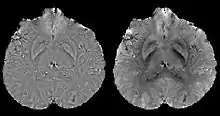

Differentiating calcification from iron

It has been confirmed in in vivo and phantom experiments that cortical bones, whose major composition is calcification, are diamagnetic compared to water.[11][18] Therefore, it is possible to use this diamagnetism to differentiate calcifications from iron deposits that usually demonstrate strong paramagnetism.[19] This may allow QSM to serve as a problem solving tool for the diagnosis of confounding hypointense findings on T2* weighted images.